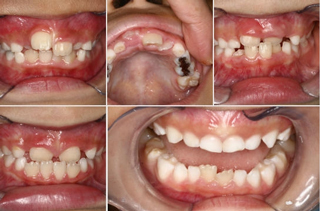

2歳になったらフッ素によるむし歯予防を始めましょう。6歳くらいになると歯の生え変わりが始まります。6歳になったら歯のはえかわりのチェックを受けるようにしてください。美馬市周辺の子どもは正中埋伏過剰歯が他地域より多いと感じています。適切に抜歯することによって、前歯がきれいにはえやすくなります。永久歯にも影響しますので乳歯の虫歯も放置せず予防処置を受けましましょう。最近は食べる・話す・呼吸などの機能が十分に発達していない子供が増えています。当院では正常な機能を獲得してもらうためのトレーニングや歯列育成、咬合誘導をしています。小児歯科は副院長の担当になります。

子どもの場合、矯正治療を開始するのに適した時期は症状によって異なりますが、だいたい永久歯が生え始める6~7歳で矯正治療を始めるのが最適で、治療期間が短くて済むことが多いです。

当院では「7歳までに歯並びと咬み合わせのチェックを!」と呼びかけています。この頃は乳歯から永久歯に生え変わる時期で、顎の成長が旺盛なため、矯正治療において非常に大切な骨格的なバランスを治療できる可能性があるからです。ただ矯正治療は本人自身の協力が不可欠なため、本人が矯正したくなったときが治療に最適な時期とも言えます。